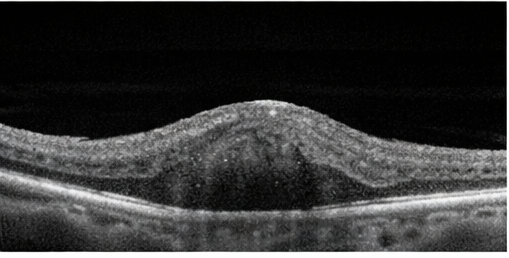

Fundus photography demonstrated a localized, elevated vascular lesion with characteristic coloration. Optical coherence tomography (OCT) revealed mild retinal thickening overlying the lesion, without significant subretinal fluid.

Based on clinical appearance and imaging findings, a diagnosis of ocular hemangioma most consistent with a circumscribed choroidal hemangioma was made. Differential diagnoses considered included choroidal melanoma, metastatic lesion, and central serous chorioretinopathy; however, the lesion’s color, borders, and lack of associated risk features favored a benign vascular etiology.

Multimodal imaging plays a pivotal role in establishing an accurate diagnosis and guiding management. Fundus photography allows documentation of lesion size, color, and progression over time, while optical coherence tomography (OCT) provides detailed cross-sectional imaging of the retina and choroid, enabling detection of subretinal fluid, retinal thickening, and macular involvement. B-scan ultrasonography typically demonstrates a highly reflective, acoustically solid lesion, which helps distinguish hemangiomas from choroidal melanomas. Fluorescein angiography further aids differentiation by revealing early hyperfluorescence with late staining, a pattern characteristic of vascular tumors [5]. In selected cases, indocyanine green angiography may offer additional diagnostic clarity.